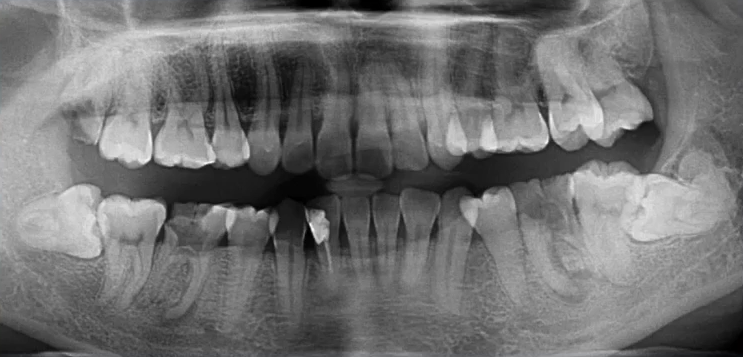

因为曲面断层片反映的是上下颌牙齿、上颌窦、关节,在一张片子中所展示的解剖结构较多。比如刚才的片子,最容易诊断的是右下6远中邻面深龋合并根尖周炎,左下有埋伏的多生智齿,右侧是垂直智齿。

注意不要遗漏,比如片子中显示上颌两个3是缺失的,是先天性缺失还是做过手术?有可能会漏掉一些临床信息。

32岁,男性,因咬物不适来院就诊。

查:14残根,牙龈红肿;35叩诊(+),45叩诊(+),牙颌面见畸形中央尖。

临床检查时发现14残根,牙龈红肿。曲面断层片上由于前磨牙转角问题,看不到残根,无法明确到底有没有残根,无法通过曲面断层片进行确诊或评估。

18残根、38牙根方高密度影、36根尖炎、46根尖炎

48水平阻生

42根管内充填影,未到根尖

其他问题:14、24、34、44牙缺失,为什么?

45根尖有阴影,是不是炎症?那35根尖呢?

36、46只是根尖炎?

42根尖有没有囊肿?